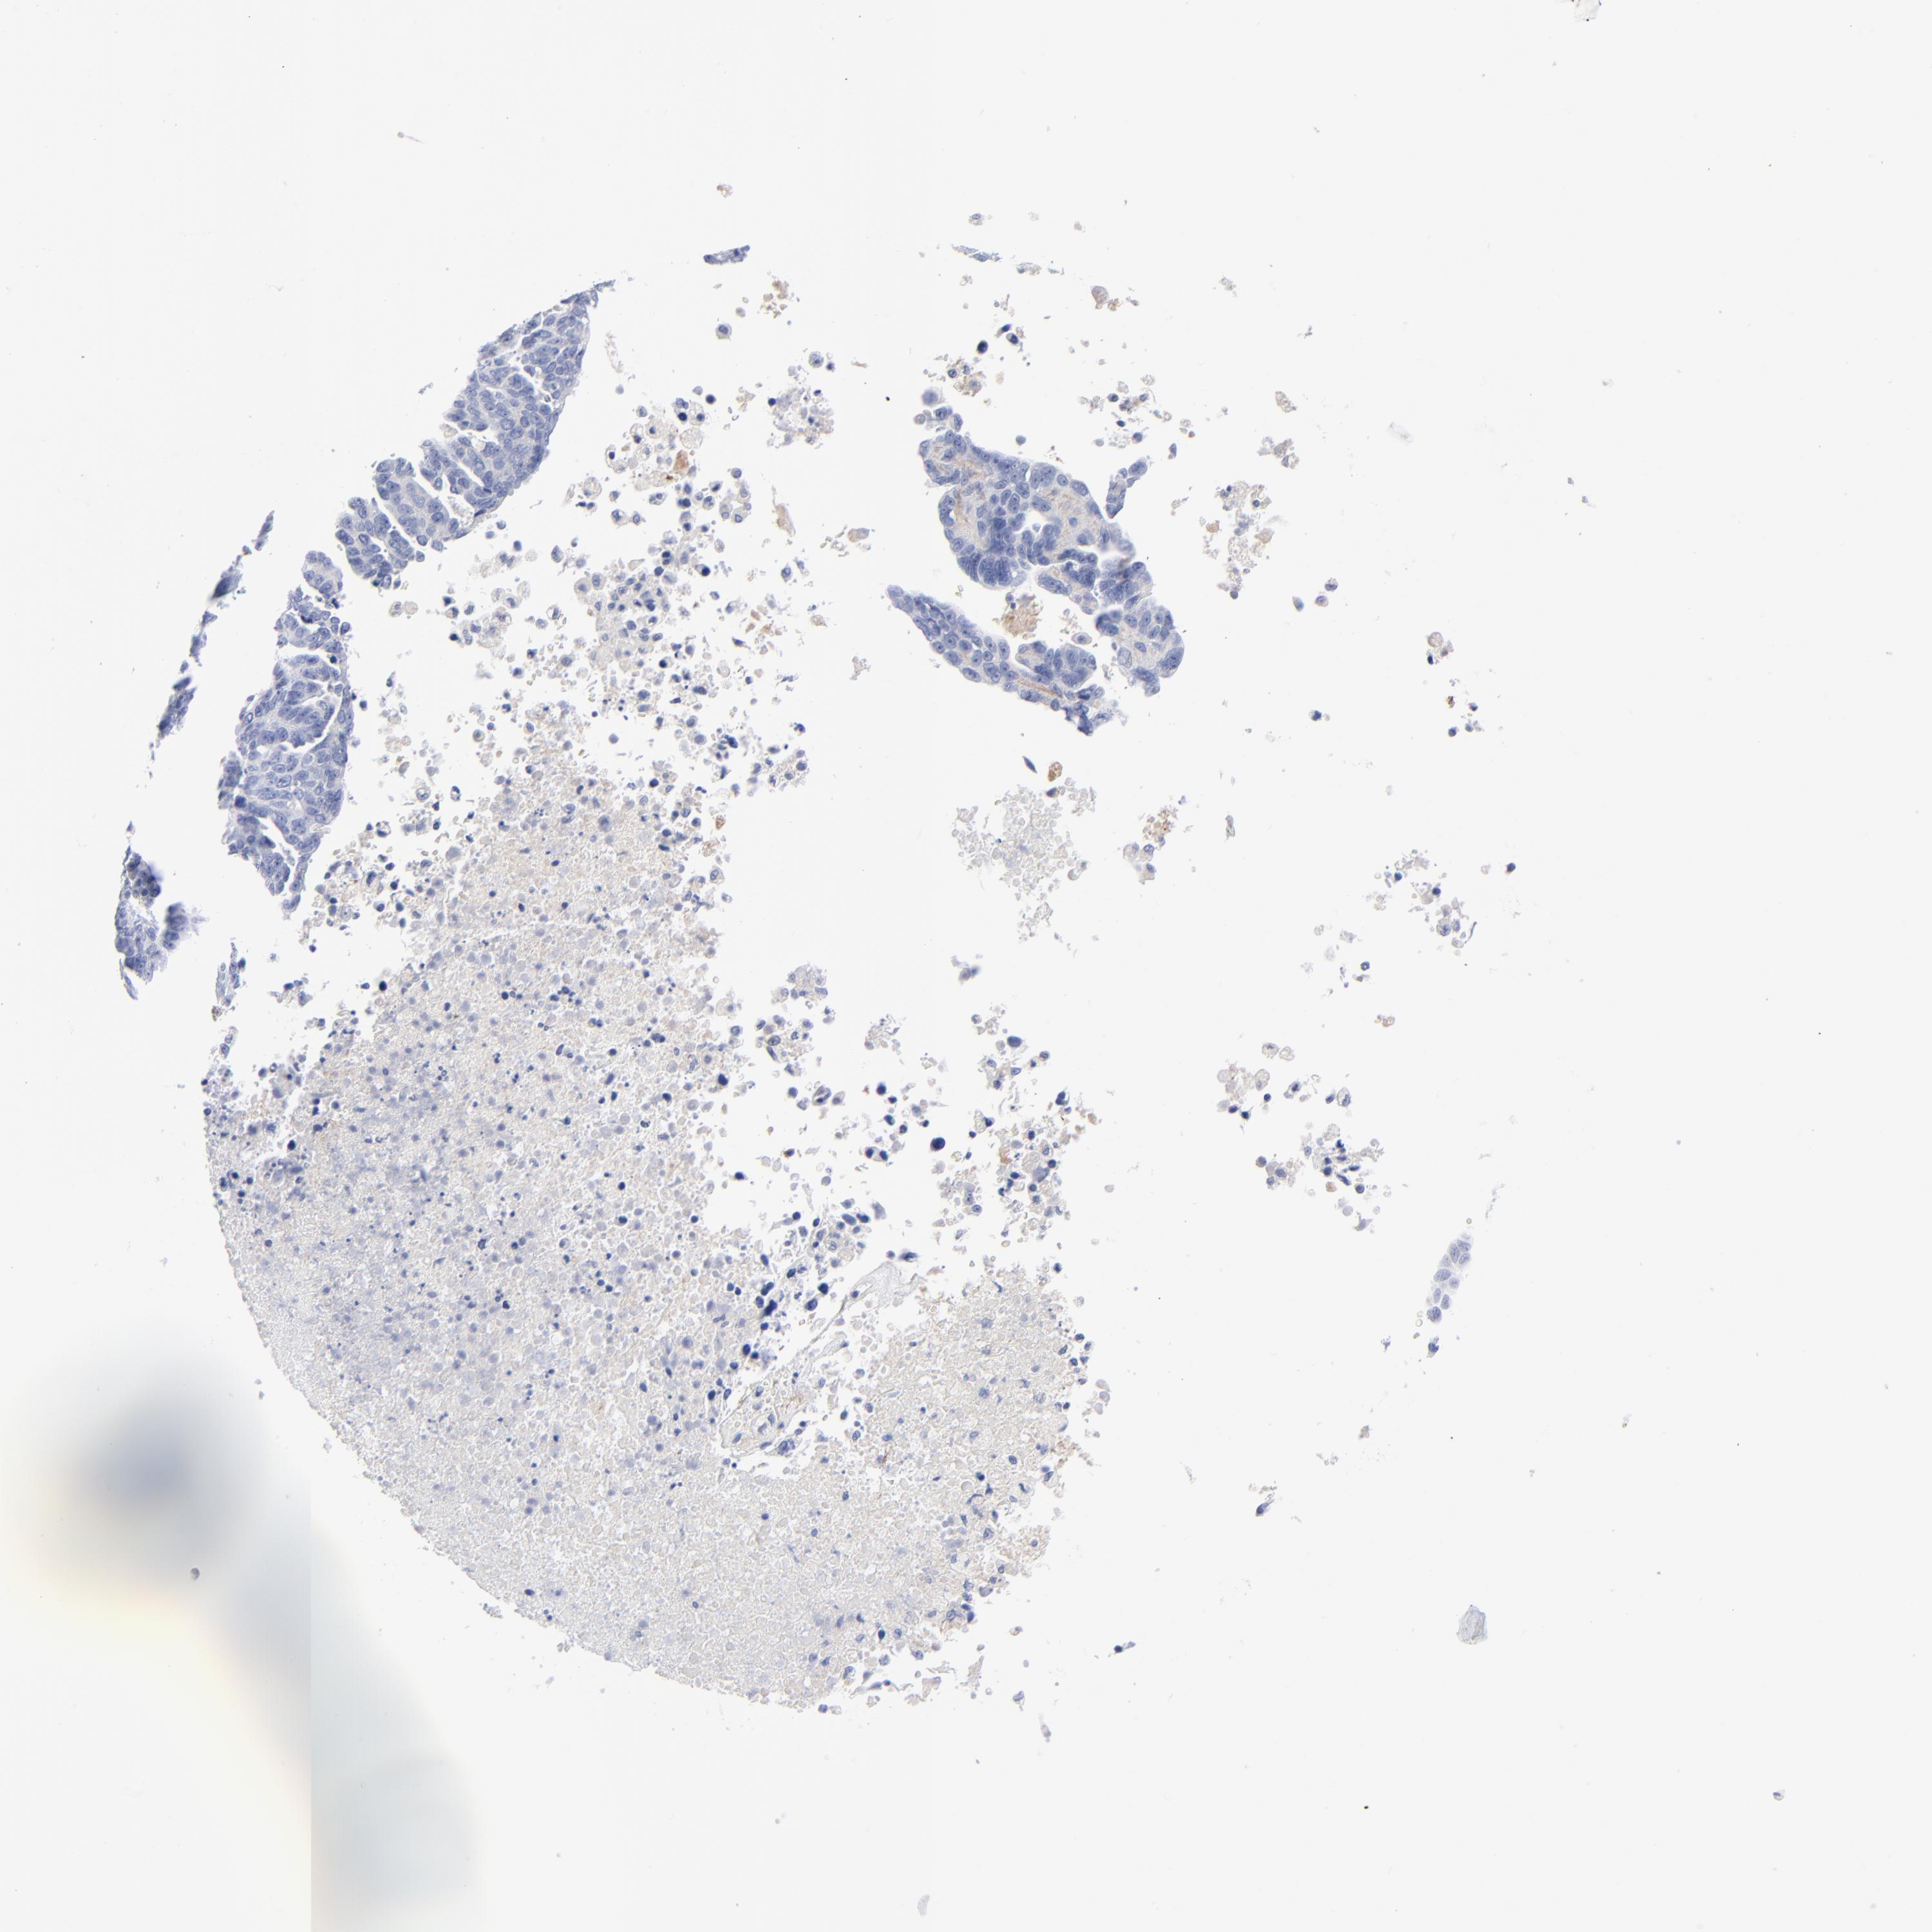

OVARIAN CANCER - Protein expressioni

A mouse-over function shows sample information and annotation data. Click on an image to view it in a full screen mode. Samples can be filtered based on level of antibody staining by selecting one or several of the following categories: high, medium, low and not detected. The assay and annotation is described here.

Note that samples used for immunohistochemistry by the Human Protein Atlas do not correspond to samples in the TCGA dataset.

Antibody stainingi

Antibody staining in the annotated cell types in the current human tissue is reported as not detected, low, medium, or high, based on conventional immunohistochemistry profiling in selected tissues. This score is based on the combination of the staining intensity and fraction of stained cells.

Each image is clickable and will lead to virtual microscopy that enables deeper exploration of all samples and also displays staining intensity scores, fraction scores and subcellular localization as well as patient and tissue information for each sample.

Antibody HPA001934

Antibody CAB018622

Staining

High

Medium

Low

Not detected

Intensity

Strong

Moderate

Weak

Negative

Quantity

>75%

75%-25%

<25%

None

Location

Nuclear

Cytoplasmic/membranous

Cytoplasmic/membranous,nuclear

Cystadenocarcinoma, mucinous, NOS

Carcinoma, endometroid

Cystadenocarcinoma, serous, NOS

Carcinoma, NOS